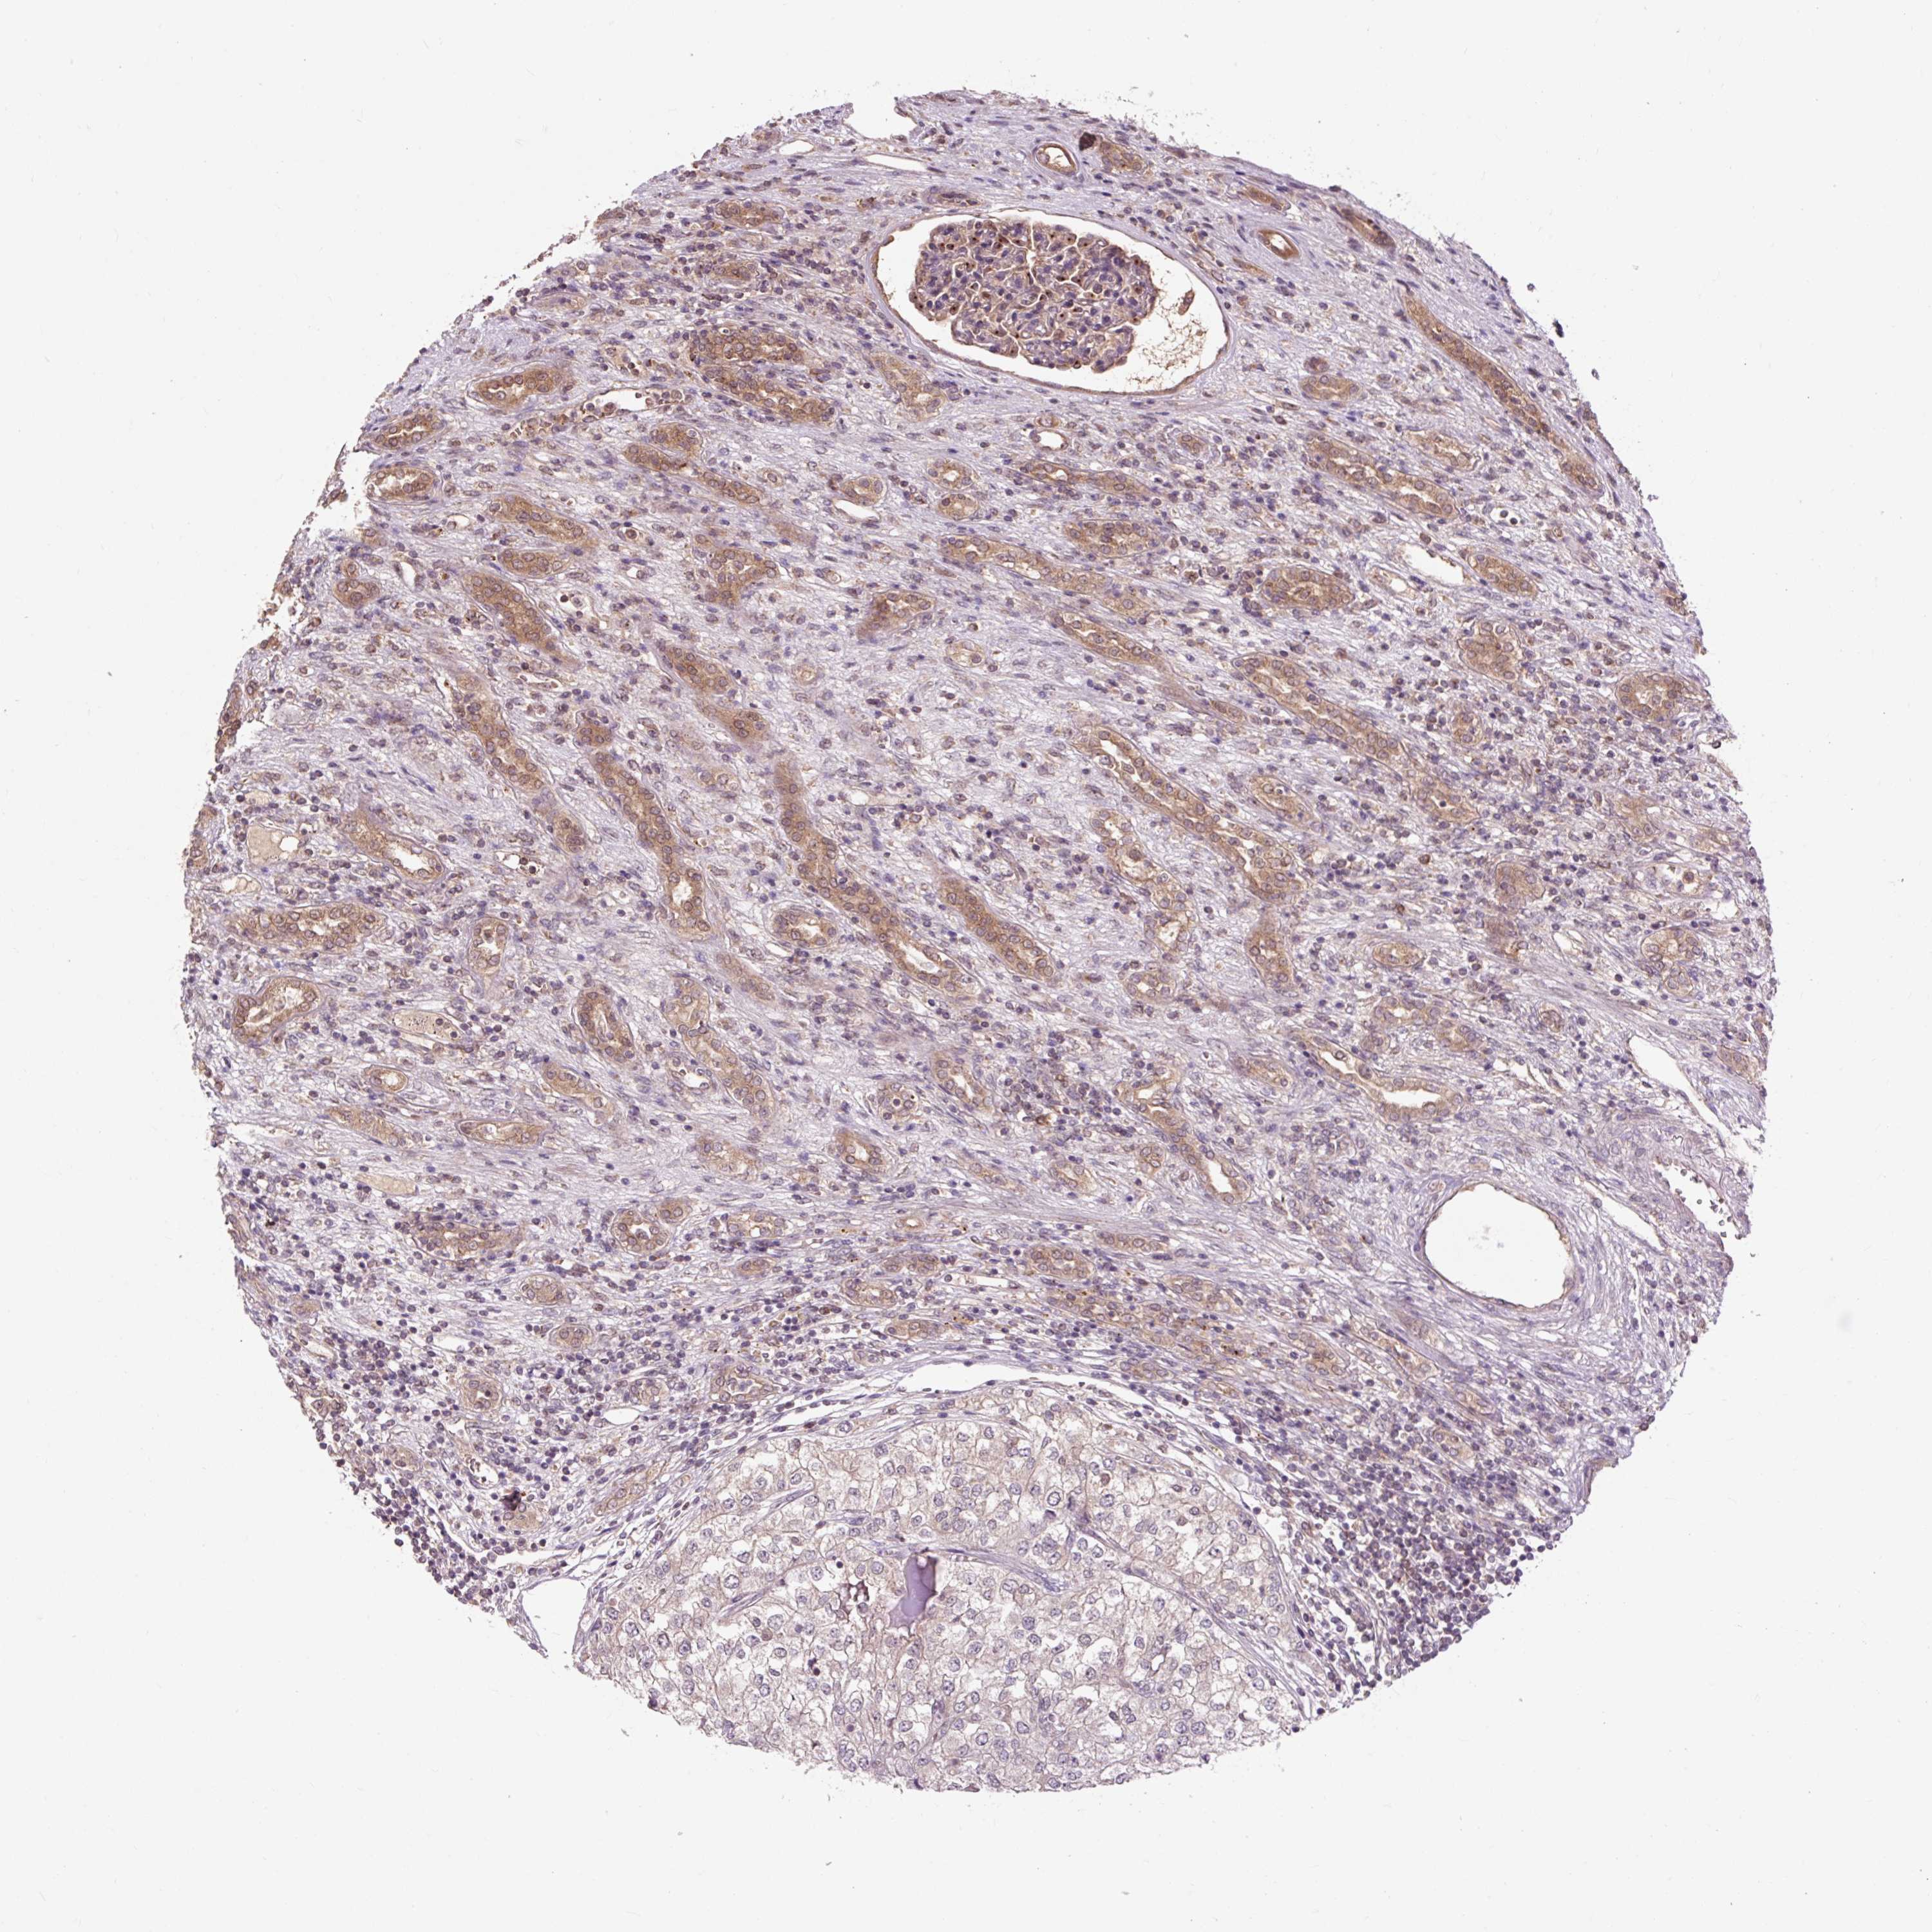

TCGA RNA samplesi

RNA-seq data is reported as average FPKM (number Fragments Per Kilobase of exon per Million reads), generated by the The Cancer Genome Atlas (TCGA) .

Normal distribution across the dataset is visualized with box plots, shown as median and 25th and 75th percentiles. Points are displayed as outliers if they are above or below 1.5 times the interquartile range. FPKM values of the individual samples are presented next to the box plot.

Average pTPM 23.3

Number of samples 100